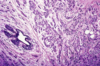

What is this showing?

Apocrine metaplasia, which is almost always benign